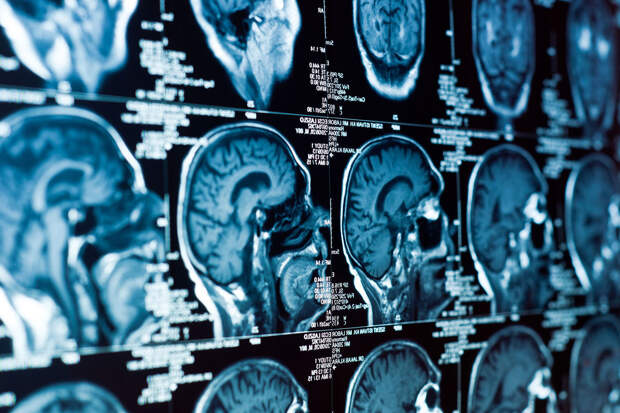

Ученые объяснили: человеческий мозг отличается от мозга других животных масштабной корой, сложной организацией и большим разнообразием клеток.

Эти особенности закладываются еще в период развития, в вентрикулярной зоне — области, где стволовые клетки дают начало нервным и вспомогательным клеткам. Чтобы делиться и мигрировать в нужные слои, клетки постоянно перестраивают цитоскелет — внутренний "каркас", определяющий их форму и направление роста.Исследователи установили, что ARHGAP11A контролирует эти процессы. Когда ген работает корректно, стволовые клетки сохраняют ориентацию, остаются в нужном месте и делятся в нужном темпе. При его отсутствии клетки раньше времени покидают ткань и превращаются в нейроны. Это приводит к быстрому истощению резерва стволовых клеток и нехватке опорных клеток, которые необходимы для созревания и стабильности мозга.

Работа проводилась на органоидах — моделях человеческого мозга, выращенных из стволовых клеток. Они позволили увидеть, как нарушение работы ARHGAP11A изменяет архитектуру развивающейся ткани. Кратковременное подавление чрезмерно активных сигнальных путей частично устраняло эти дефекты, что говорит о потенциальной управляемости процесса.